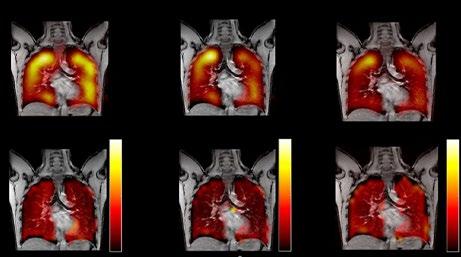

48 Editor's Pick: Clinical Applications of Hyperpolarised Xenon-129 MRI

Ng et al.